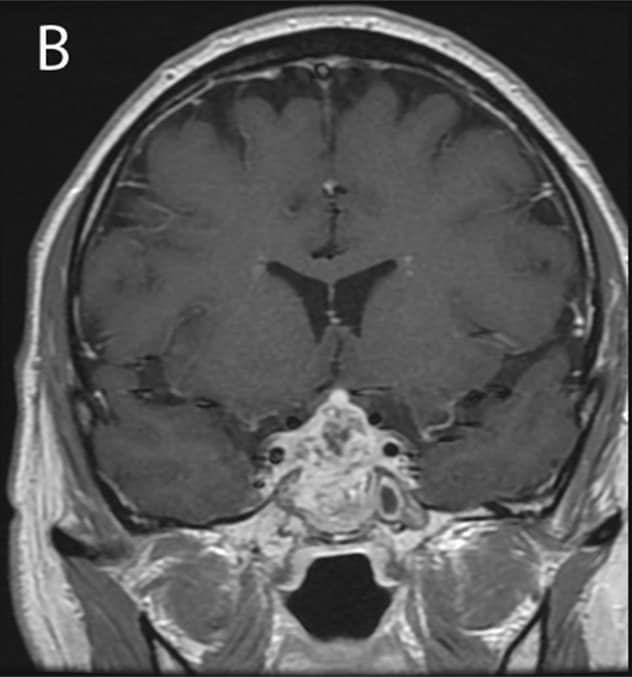

Enlarging sellar mass at three months

Enlarging sellar mass at three months

Three months after initial presentation: Enlarging sellar mass with extension into the sphenoid and cavernous sinuses on MRI.

The patient was treated empirically with a course of ertapenem. Three months later, he developed worsening headache, fever, chills and visual changes. MRI showed the pituitary mass was extending into the sphenoid and cavernous sinuses. A pituitary biopsy was inconclusive. Eventually, culture of his cerebrospinal fluid grew Nocardia farcinica approximately one month after collection.